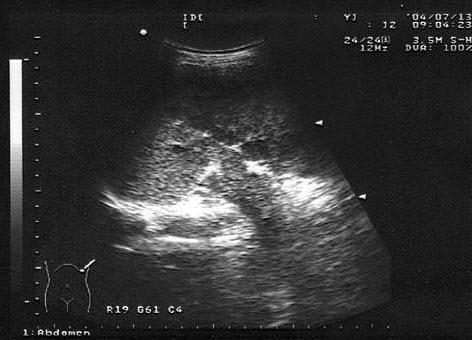

11、单项选择题

患者女47岁,皮肤、巩膜黄染,进行性加重2个月余,腹痛、腹胀,既往有胆结石病史。B超检查如图所示,根据超声声像图,诊断为()

A.胆总管癌并结石

B.胆总管胆泥淤积

C.胆总管结石

D.胆总管蛔虫

E.胆总管癌